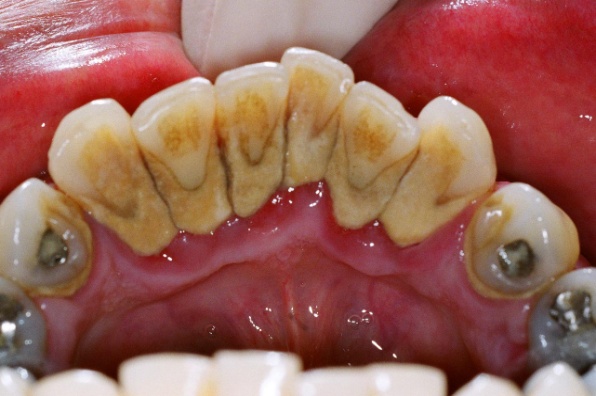

Heavy calculus (tartar) deposits on the inside aspect of the lower incisor teeth in a patient with periodontitis.